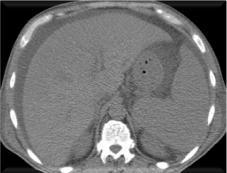

Light-chain deposition disease (LCDD) is a rare monoclonal gammopathy that involves the deposition of light chains (LC) in multiple organs, leading to progressive dysfunction. The kidney is usually the most affected organ and responsible for the initial clinical manifestations. We present the case of a patient with LCDD with prominent liver involvement (marked cholestasis, hepatomegaly and portal hypertension) but with no evidence of coexisting lymphoproliferative disorder.

轻链沉积病(LCDD)是一种罕见的单克隆丙种球蛋白病,涉及轻链(LC)在多个器官中的沉积,导致进行性功能障碍。肾脏通常是受影响最严重的器官,也是初始临床表现的原因。我们报告一例LCDD患者,其肝脏受累显著(明显胆汁淤积、肝肿大和门静脉高压),但无并存淋巴增殖性疾病的证据。